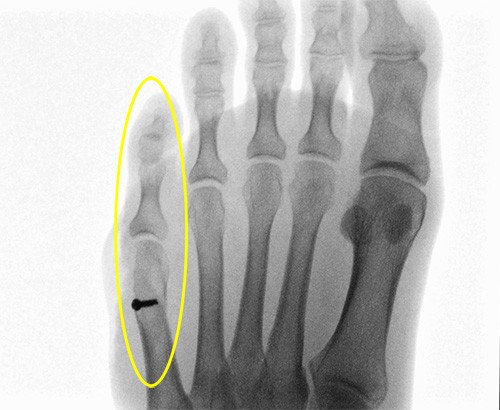

Unsere Patientin stellt sich sechs Wochen nach der Operation erneut in unserer Sprechstunde zur Kontrolle vor, zuvor war sie durch ihren Hausarzt ohne Auftreten von Problemen betreut worden, meist wird eine Nachbehandlung direkt bei uns durchgeführt. Nach vier Wochen wurde eine Röntgenaufnahme der Patientin – auf Wunsch der Patientin - beim Hausarzt angefertigt und hier eine zunehmende Durchbauung (Heilung) des Knochens festgestellt.

Die Patientin konnte ab diesem Zeitpunkt nun langsam versuchen wieder normales Schuhwerk zu tragen, dies ist aufgrund der meist noch bestehenden Schwellung nicht immer schnell möglich. Manchmal muss das Tragen der normalen Schuhe schrittweise geübt werden. Die Patientin ist mit dem Ergebnis der Operation sehr zufrieden, berichtet über nahezu keinerlei Beschwerden mehr, sie trägt bei der Konsultation bei uns bereits normales Konfektionsschuhwerk, allerdings noch mit flacher Sohle. Es besteht noch eine leichte Schwellung, diese kann noch Monate nach der Operation vorhanden sein. Eine physiotherapeutische Beübung wurde der Patientin zum schnelleren Abschwellen des Fusses angeboten, sie wollte darauf verzichten. Sportliche Aktivitäten wie Tennis können erst nach ca. 3 Monaten wieder begonnen werden. Später können auch wieder Schuhe mit Absatz getragen werden. Wir empfehlen noch eine Narbensalbe, um die Narbe schneller weniger sichtbar zu machen sowie einen adäquaten Sonnenschutz, insbesondere über den Sommer, um Überpigmentierungen der Narbe zu vermeiden.